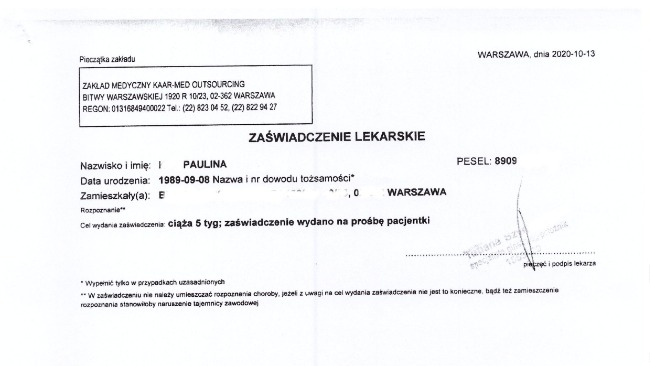

10 października okazało się, że jestem w 5 tygodniu ciąży, to był najpiękniejszy prezent imieninowy jaki dostałam. Napisałam szybko do pracodawcy, że w tym wypadku wnoszę o wycofanie rozwiązania umowy ponieważ nie wiedziałam, że jestem w ciąży podpisując je.